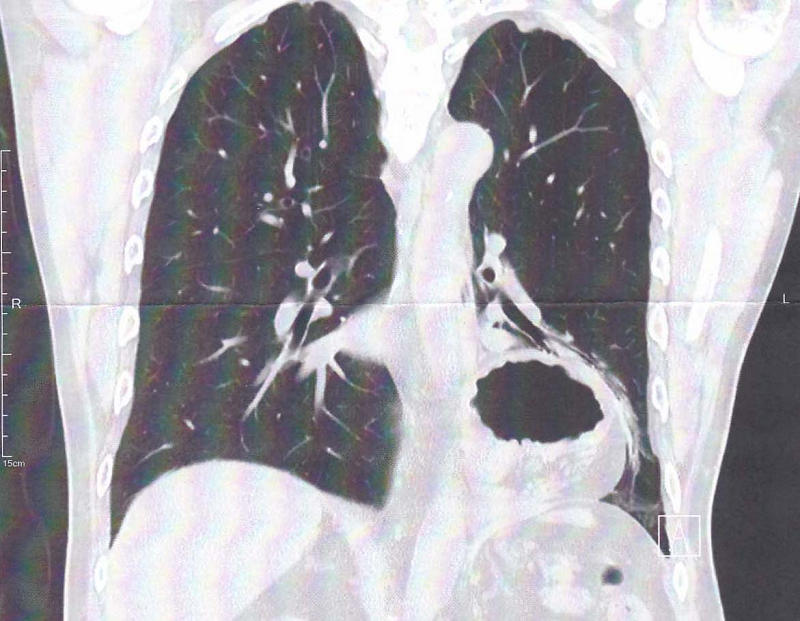

血液検査、レントゲン、CT検査を受けた結果、やはり食道裂孔ヘルニアが再発していることが判明しました。

食道裂孔ヘルニアが再発しました。

これでもう大丈夫と思っていたのですが、昨年末に腹痛で地元の病院に救急搬送されて腸閉塞と診断された際の検査で、また横隔膜の上に影が見えていました。